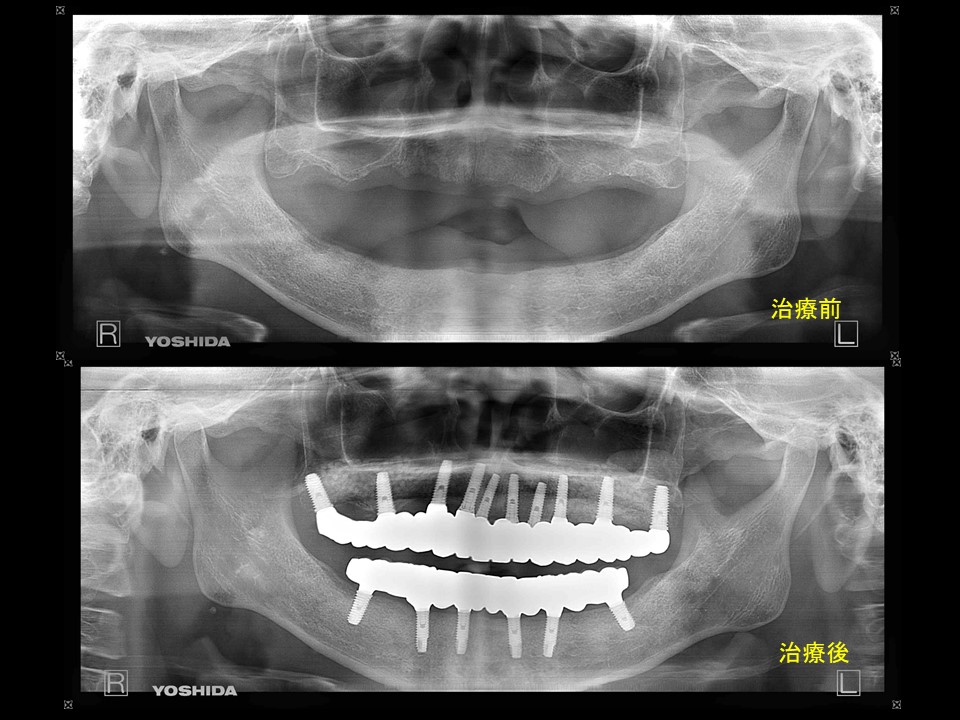

症例7